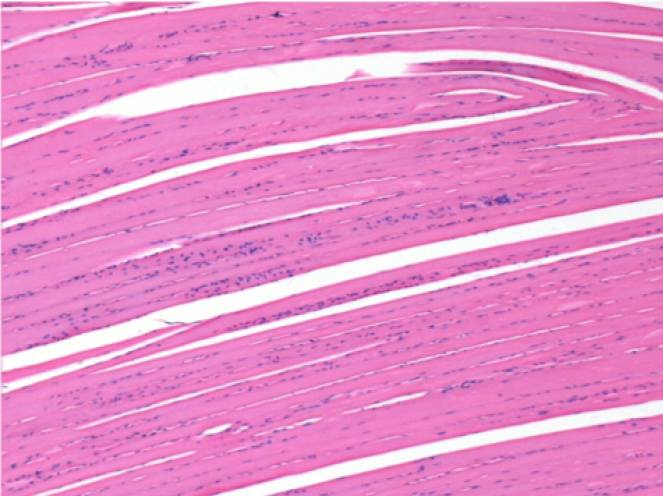

7 meses después de la inyección de Endopeel

7 meses (D210) después de la inyección IM de Endopeel 0,1 ml en el músculo pretibial derecho.

Restitutio ad integrum (restauración a la condición original) completa después de 7 meses

L : Control-100xD210

R:100xD210

L :Control 50xD210

R50X-D210